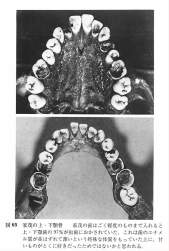

戦国武将の歯の写真が残ってるのすごいな

>戦国武将の歯の写真が残ってるのすごいな

江戸時代の将軍です…

>徳川 家茂(とくがわ いえもち)は、江戸幕府第14代将軍

>慶応2年7月20日(1866年8月29日)(20歳没)

虫歯だらけなわりに歯は綺麗に揃ってんなと思ったらすんごく若かった…

将軍としては期待の逸材だったらしいからかわいそう(本人と江戸幕府が)

こんな歯なのに脚気による病気で倒れた時に甘党なの知られてたから

全国の大名からのお見舞い品が饅頭や最中とか甘い物ばっかりだったという…